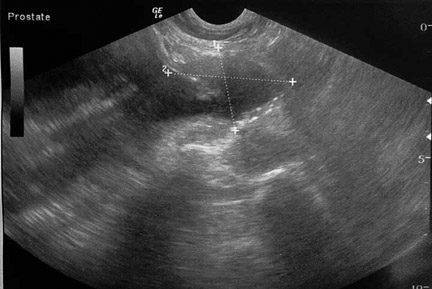

This is what the prostate gland looks during ultrasound